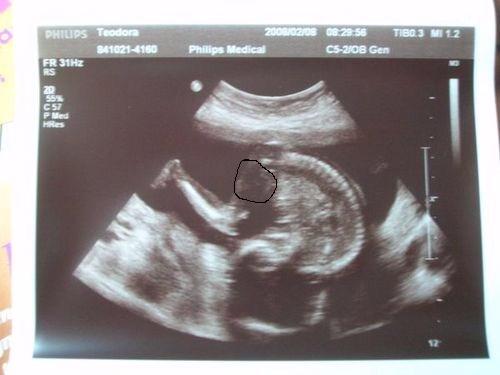

Dodo! Úgy drukkoltam Neked is a reggeli UH-hoz, de már látom meg is jöttél!

Örülök, hogy minden rendben.... a meglepi meg meglepi és kész!